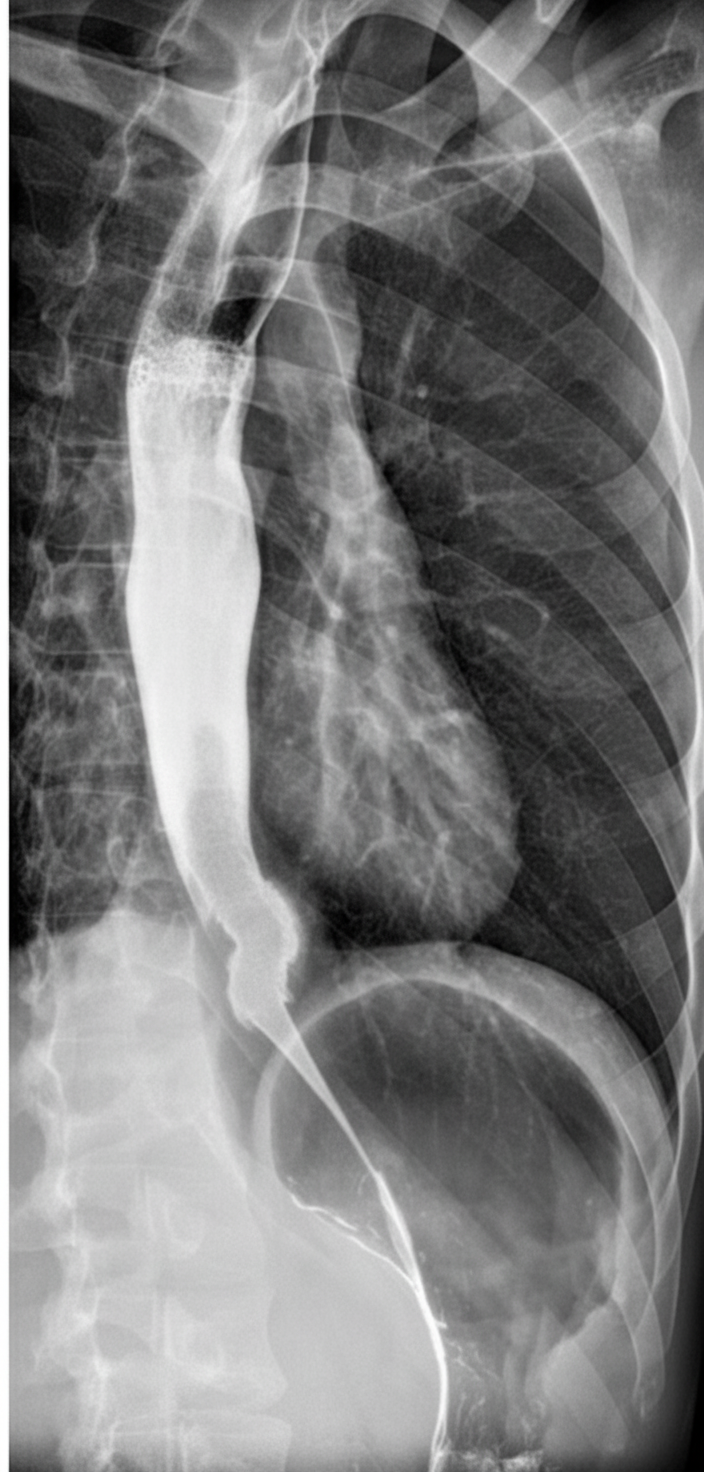

A barium swallow shows which of the following findings?

Explanation: ***Carcinoma esophagus*** - Shows classic **irregular filling defect** with **shouldering** and **rat-tail** or **apple-core appearance** on barium swallow. - Demonstrates **abrupt luminal narrowing** with **mucosal irregularities** and **asymmetric wall thickening**. *Achalasia cardia* - Presents with characteristic **bird-beak appearance** showing smooth tapering at the gastroesophageal junction. - Associated with **dilated esophageal body** above the narrowed lower esophageal sphincter, unlike the irregular stricture seen in carcinoma. *Nut cracker esophagus* - Primarily a **manometric diagnosis** based on high-amplitude peristaltic contractions (>180 mmHg). - Barium swallow typically appears **normal** or may show mild tertiary contractions, not the filling defect pattern described. *Oesophageal stricture* - Shows **smooth, symmetrical tapering** with regular mucosal outline on barium studies. - Lacks the **irregular shouldering** and **asymmetric narrowing** characteristic of malignant lesions.